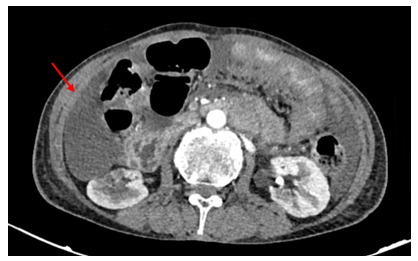

Chụp CT ổ bụng có tiêm thuốc cản quang:

Hình 2: Dày lan tỏa phúc mạc, ngấm thuốc mạnh sau tiêm (mũi tên đỏ).

Hình 3: Dịch tự do ổ bụng, chỗ dày nhất 53 mm (mũi tên vàng).